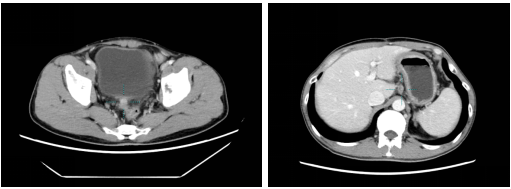

2021.08.16 胸部CT示:双肺多发小结节,与前相仿;

腹部CT示:1. 胃癌术后,胃壁增厚较前变薄、腹膜转移灶(1.2×0.9cm),与前相仿;2. 肝胃间隙稍大淋巴结(1.3×1.4cm),与前相仿。

2021.10.18 胸部CT示:双肺多发小结节与前相仿;

腹部CT示:1. 胃癌术后,腹膜转移灶(1.2×0.9cm),与前相仿;2. 肝胃间隙稍大淋巴结(1.3×1.4cm),与前相仿。

2022.01.05 胸部CT示:双肺多发小结节与前相仿;

2022.03.08 胸部CT示:双肺多发小结节与前相仿;

腹部CT示:1. 胃癌术后,腹膜转移灶(1.3×0.9cm),与前相仿;2. 肝胃间隙稍大淋巴结(1.3×1.0cm),与前相仿。